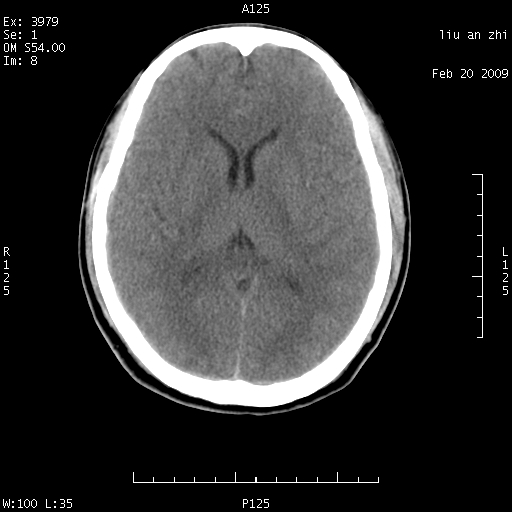

7天后复查头颅ct片:

小脑幕前后7天变化不明显,考虑正常,不考虑sah,7天应该基本吸收了。

ct18448的结果:mri检查左侧天幕下血肿